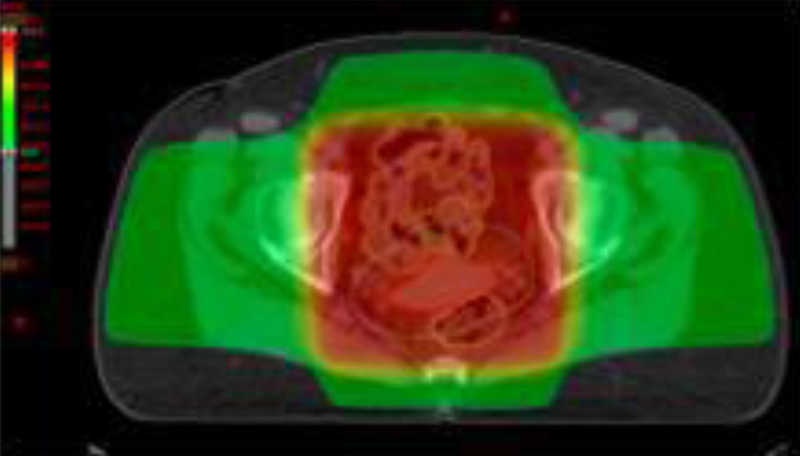

La radioterapia tridimensional conformada (RTC-3D) utiliza un planificador e imágenes de TC de la paciente en posición de tratamiento con inmovilizadores adecuados, para irradiar en forma adaptada, un volumen tridimensional. Se delimitan los volúmenes de interés (volumen a irradiar y órganos de riesgo –OARs-), como recto, vejiga, cabezas femorales e intestino delgado y grueso. Se conforman los haces de radiación de intensidad uniforme sobre el volumen a tratar. El planificador de tratamiento calcula la dosis en tres dimensiones y genera el histograma dosis-volumen (DVH), que representa gráficamente la dosis recibida por cada volumen contorneado, permitiendo la asignación de una dosis determinada a cada volumen particular (fig. 1).